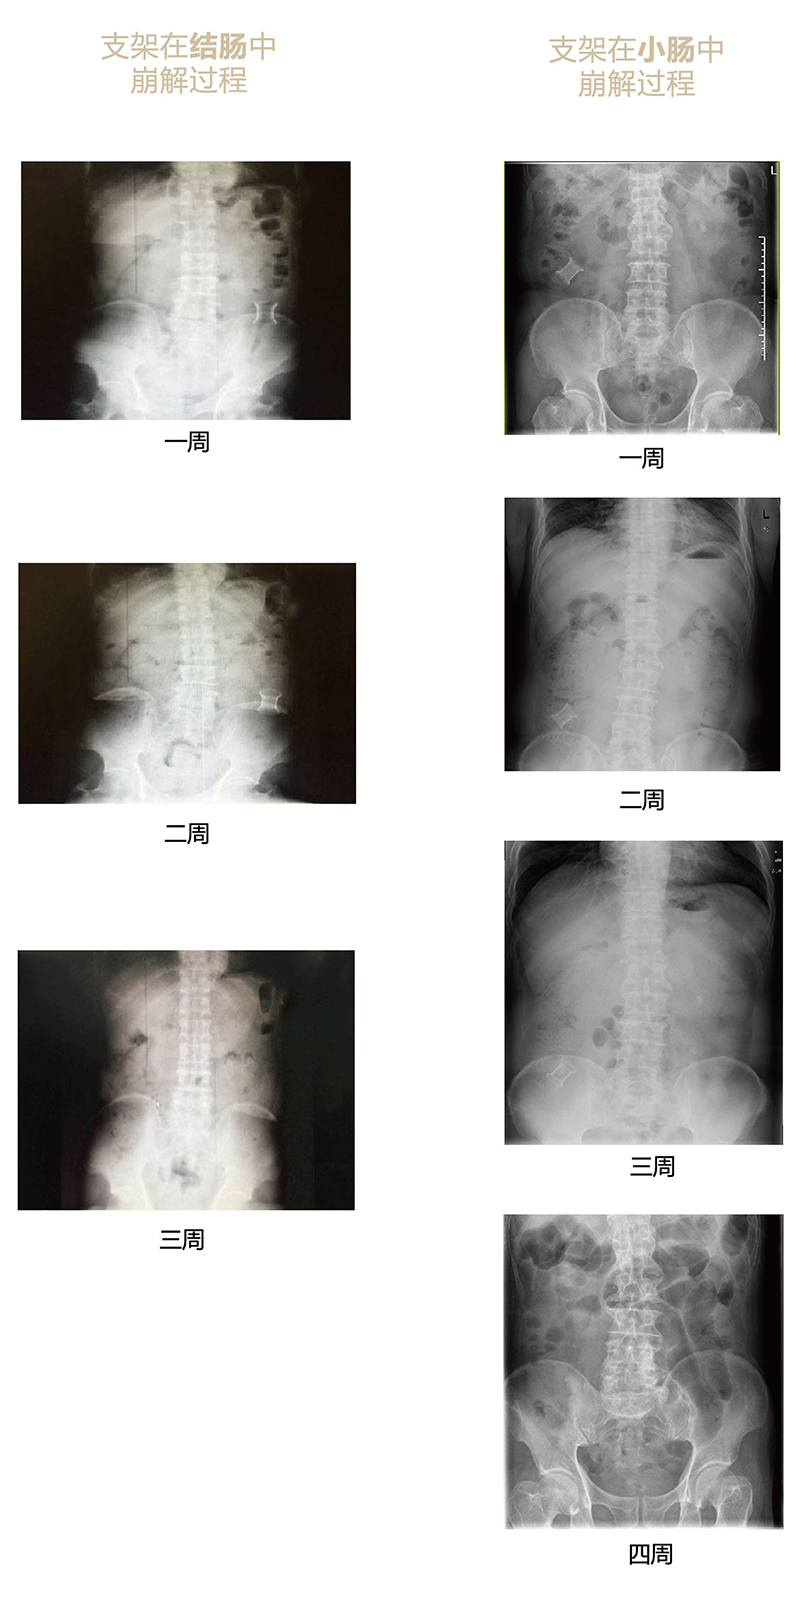

“可崩解肠道吻合器”由聚乙醇酸(PGA)与硫酸钡按重量比7:1混合注塑制成,在X线下显影,可动态追踪可崩解肠道吻合器(支架)在肠道内崩解过程。

为解决该问题,蔡秀军教授在“支架法空腔脏器吻合技术”的理念基础上,又发明了“蔡氏肠转流术”,这是一种应用“可崩解肠道吻合器HB型(可崩解肠转流支架)”(发明专利号:201910794214.3),的支架法肠道转流术,此创新术式既能保护低位吻合口,更避免了回纳术。可崩解肠转流支架在直肠癌根治术中植入远端回肠,可确保完全阻断肠腔,用肠造瘘管在转流支架近端行肠造瘘,起到完全转流的作用。肠转流支架在二至三周内逐渐崩解,并在四周内完全排出体外,恢复肠道通畅后拔除造瘘管,避免了传统造口回纳的二次手术。该创新术式具有方法简单、吻合时间短、人体内无异物永久残留、不破坏吻合口粘膜下血管,并能预防吻合口漏、可避免人工肛门留置及二次手术、治疗周期可缩短至二至四周、患者生理心理创伤显著减少。